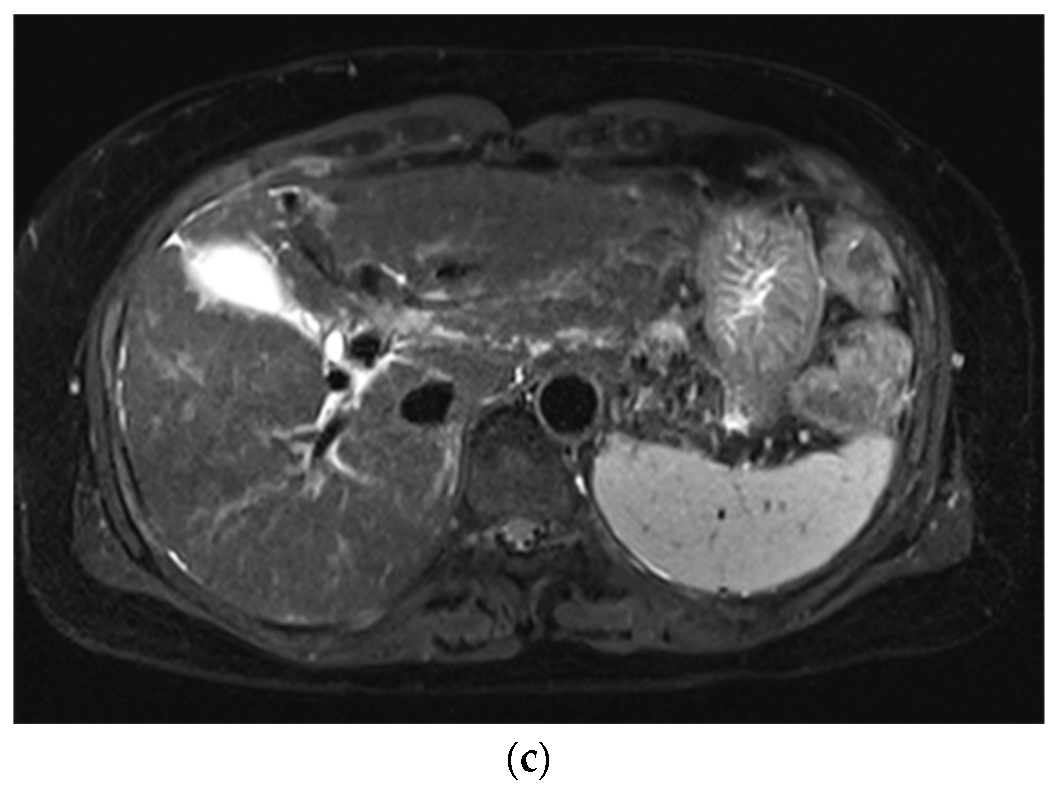

Improved Single Breath-Hold SSFSE Sequence for Liver MRI Based on Compressed Sensing: Evaluation of Image Quality Compared with Conventional T2-Weighted Sequences

3. Results

3.1. Subjective Image Quality

3.2. Lesion Assessment

4. Discussion